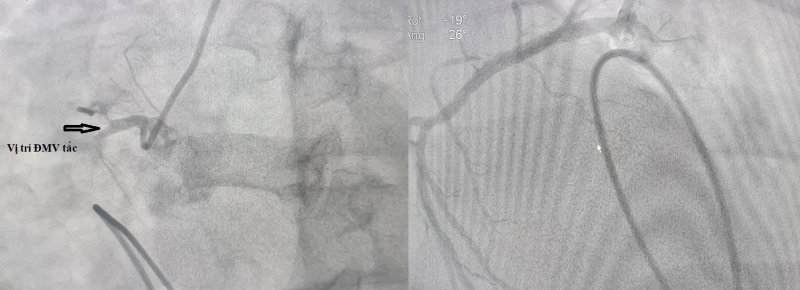

Trong quá trình theo dõi sát tình trạng và làm lại xét nghiệm men tim, sau 2 tiếng, bệnh nhân xuất hiện tình trạng đau ngực, vã mồ hôi trở lại, huyết áp tụt 60/40mmgHg, nhịp tim chậm 39 lần/phút. Ngay lập tức, các bác sĩ đã xử trí nâng huyết áp, chuyển thẳng bệnh nhân đến phòng can thiệp tim mạch đặt máy tạo nhịp tim tạm thời với điện cực trong buồng tim. Kết quả chụp mạch vành trên hệ thống chụp mạch số hóa xóa nền DSA phát hiện động mạch vành phải tắc hoàn cuối đoạn 1.

Ekip can thiệp mạch vành của Ths.BS Đinh Danh Trình – Phó Trưởng Khoa Tim mạch, Bệnh viện Bãi Cháy đã thực hiện can thiệp nong bóng, đặt 1 stent vào động mạch vành phải để tái thông dòng chảy cho mạch vành tưới máu cơ tim cải thiện. Ngay sau can thiệp, cơ tim hồi phục hoàn toàn, nhịp tim quay về nhịp xoang đều 80 lần/phút, bệnh nhân thoát nguy kịch. Sau 24h can thiệp, bệnh nhân được rút điện cực máy tạo nhịp tạm tời, không còn đau ngực, chỉ số sinh tồn ổn định.

Hình ảnh chụp mạch vành của bệnh nhân trước và sau can thiệp